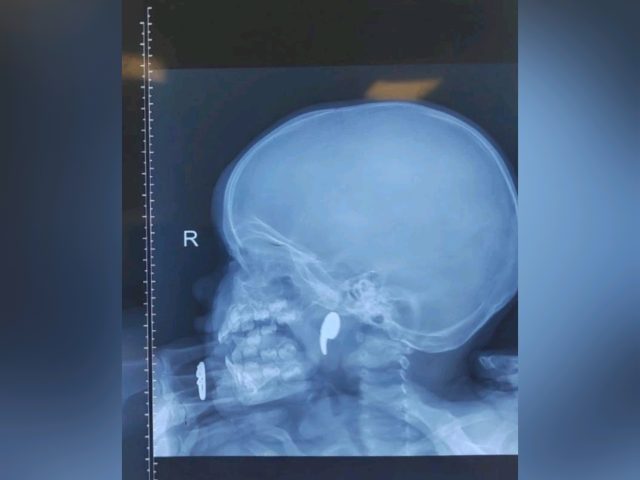

К тому моменту малышка уже жаловалась на боль в горле, отказывалась от еды, а слюнотечение стало активным. Врачи сделали рентген — на снимке отчетливо просматривалось инородное тело. Девочку немедленно госпитализировали в оториноларингологическое отделение ВОДКБ №1. Оперировала ребенка дежурный врач отделения Марина Перепечена. Под общей анестезией, с помощью эндоскопического контроля, она успешно удалила магнит. Уже через сутки девочку выписали домой. Теперь за её здоровьем наблюдает педиатр по месту жительства.